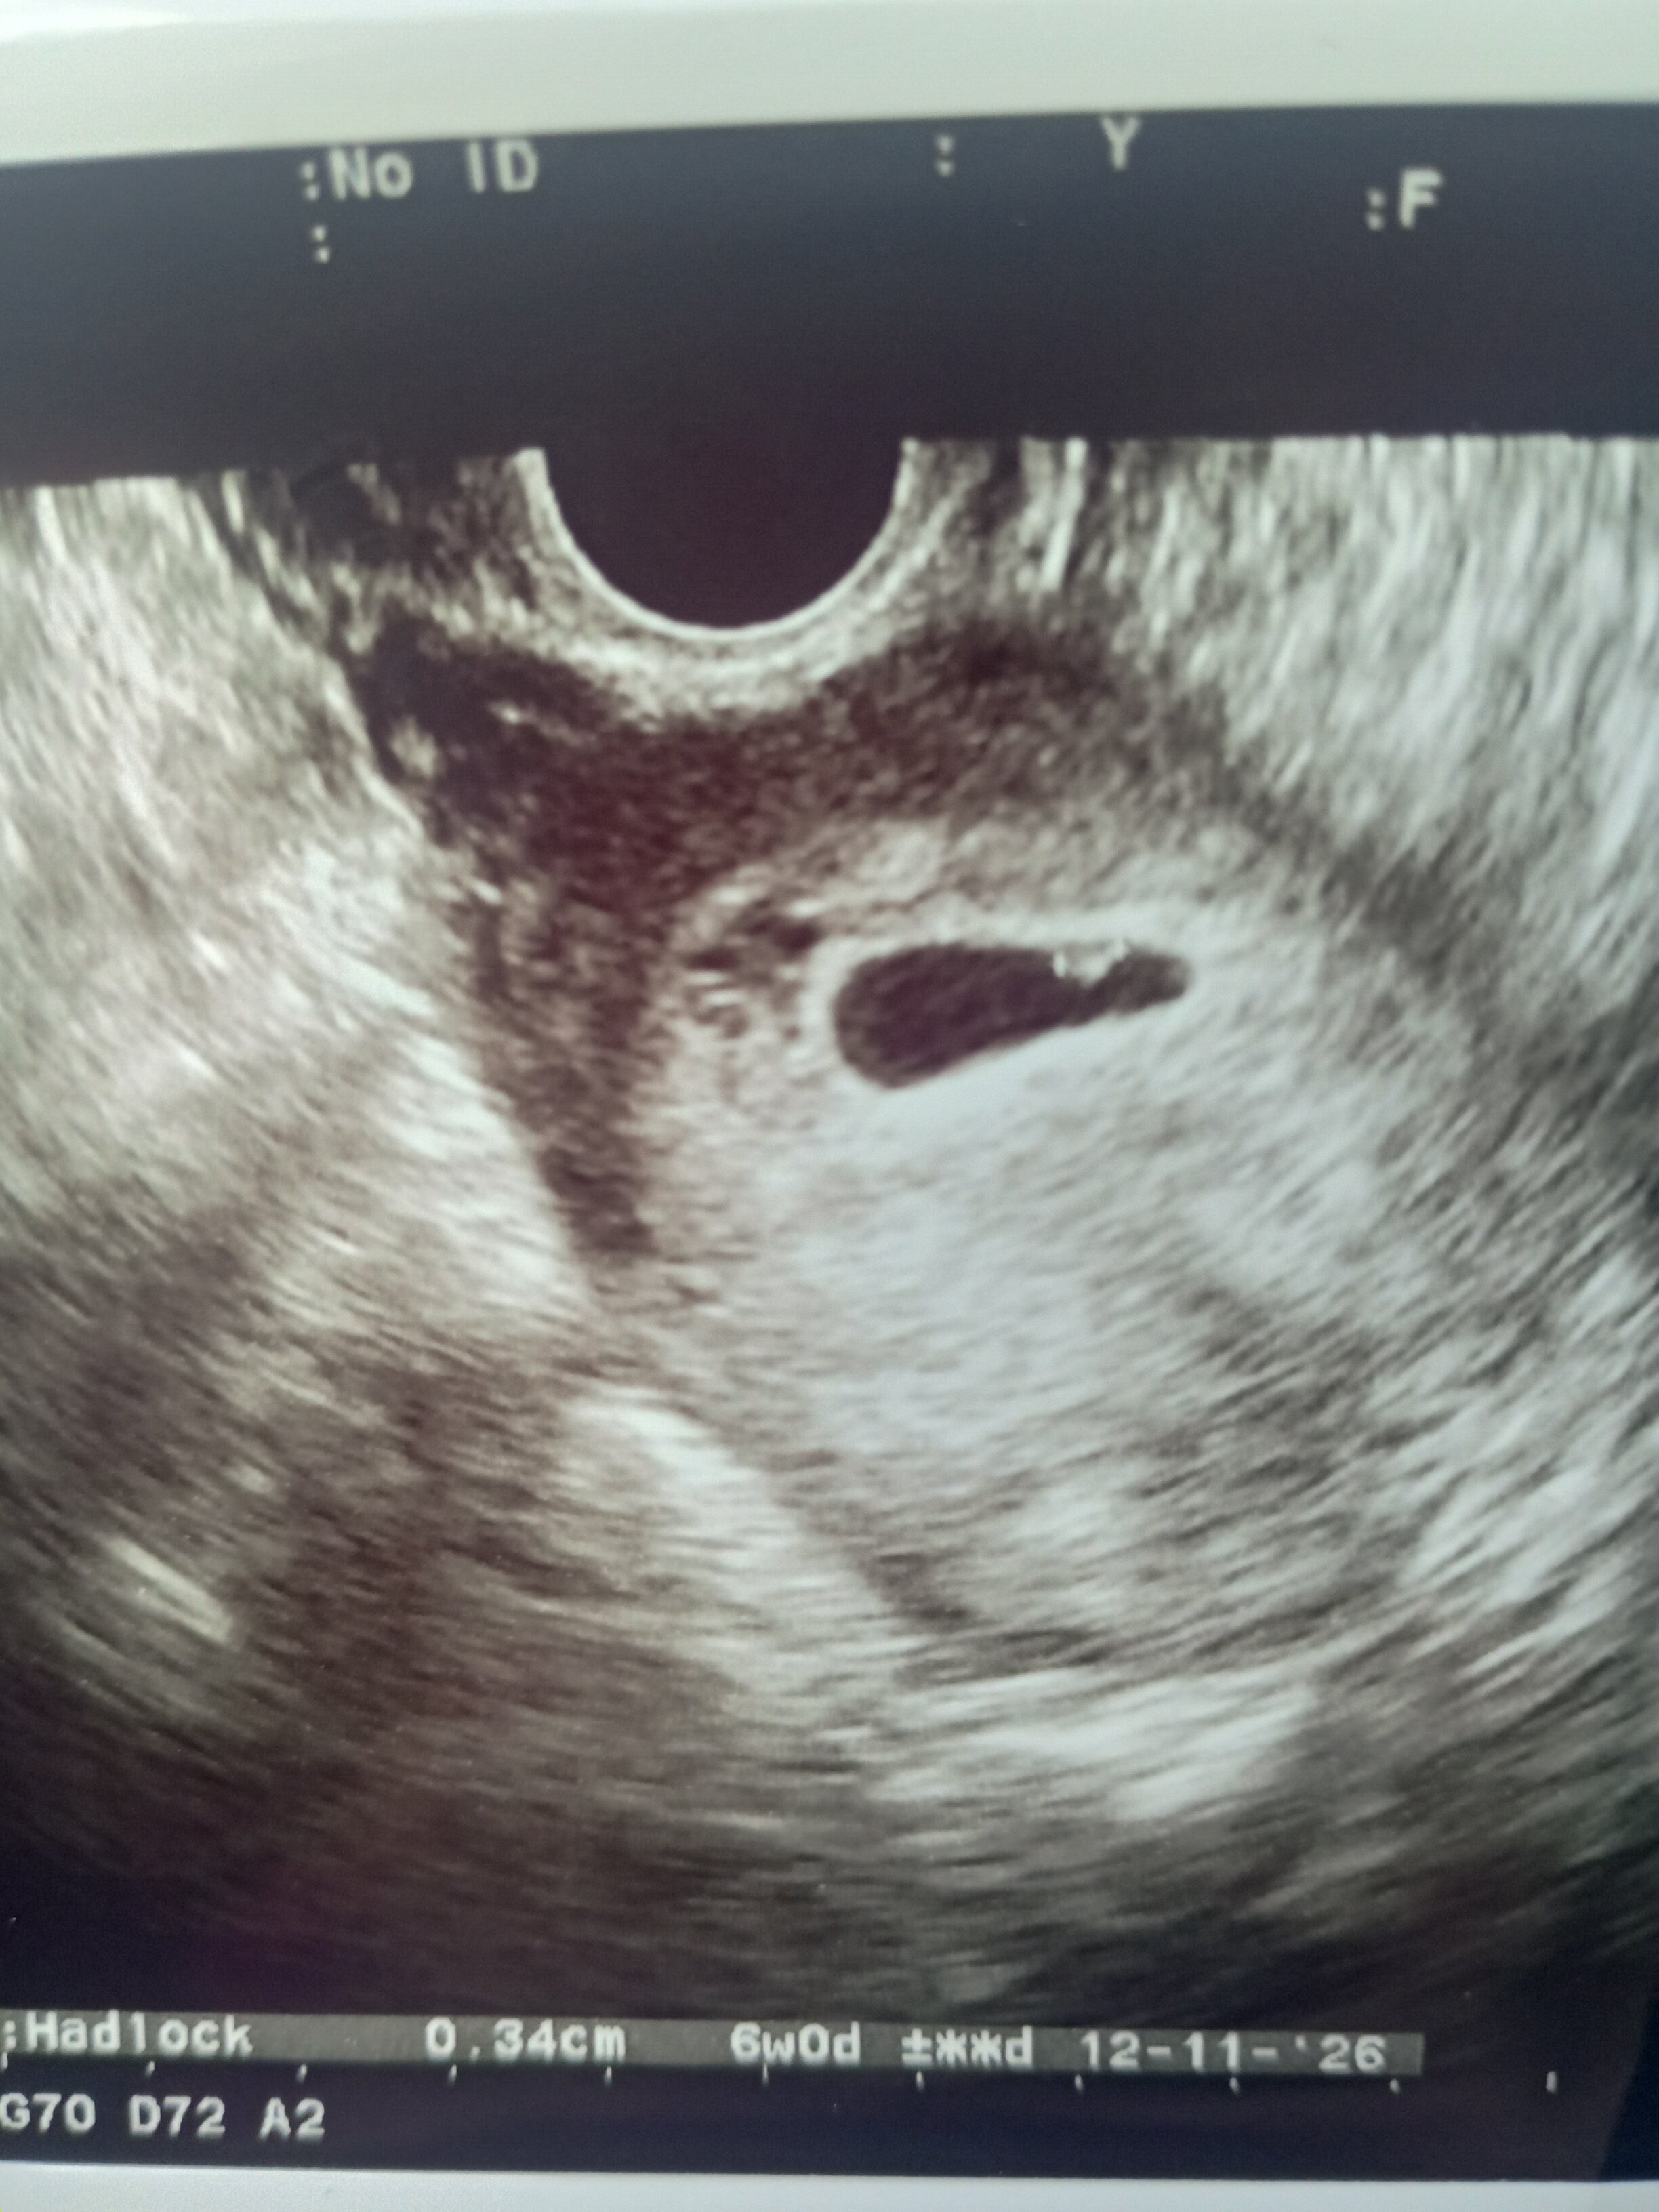

Jest bijące serduszko ❤️

Jak 💩.. dzięki że pytasz... ❤️ W następny piątek. Nie widzi takiej potrzeby.. tutaj zupełnie inaczej do tego podchodzą... Ale kurde dziwi mnie że ostatnio na sorze ordynator ginekologi szukał z 15 minut tego pęcherzyka i znalazł 0.23 a inny lekarz dzisiaj włożył USG i od razu zobaczył i tylko 0.34 więc nie rozumiem tego zupełnie.